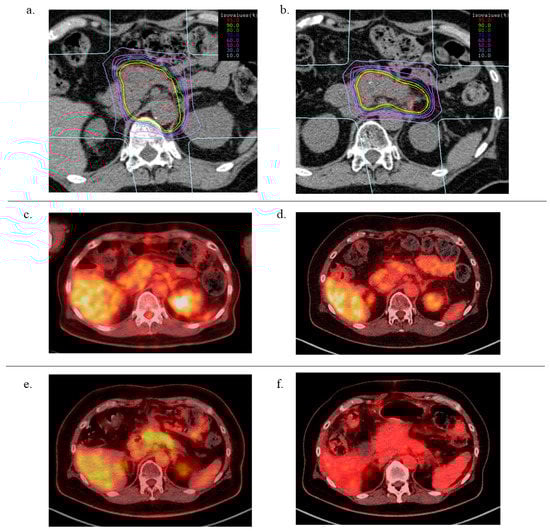

4.2. Carbon Ion Radiotherapy

4.3. Treatment Planning

| DVH Parameters | Mean (SD) | p-Value | |

|---|---|---|---|

| GTV volume (cc) | 1st CIRT | 21.9 (16.8) | 0.47 |

| 2nd CIRT | 16.6 (15.7) | ||

| CTV volume (cc) | 1st CIRT | 140.1 (37.6) | <0.001 |

| 2nd CIRT | 38.6 (22.9) | ||

| GTV V90%dose (%) | 1st CIRT | 96.8 (3.5) | 0.97 |

| 2nd CIRT | 96.7 (3.6) | ||

| GTV V95%dose (%) | 1st CIRT | 93.4 (6.3) | 0.79 |

| 2nd CIRT | 92.6 (7.1) | ||

| Stomach—D2cc (Gy(RBE)) | 1st CIRT | 32.1 (6.5) | 0.004 |

| 2nd CIRT | 17.5 (11.5) | ||

| Stomach—V30Gy (cc) | 1st CIRT | 4.3 (3.0) | 0.004 |

| 2nd CIRT | 0.7 (0.9) | ||

| Duodenum—D2cc (Gy(RBE)) | 1st CIRT | 29.5 (7.0) | 0.21 |

| 2nd CIRT | 24.9 (8.4) | ||

| Duodenum—V30Gy (cc) | 1st CIRT | 3.4 (2.8) | 0.47 |

| 2nd CIRT | 2.4 (3.0) | ||

| Intestine—D2cc (Gy(RBE)) | 1st CIRT | 32.1 (7.2) | 0.02 |

| 2nd CIRT | 22.1 (10.2) | ||

| Intestine—V30Gy (cc) | 1st CIRT | 6.4 (3.7) | 0.004 |

| 2nd CIRT | 1.7 (2.7) | ||